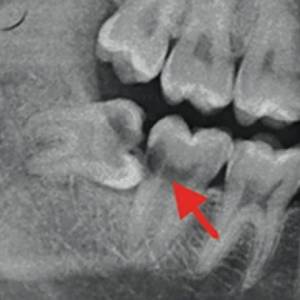

Khi nào cần nhổ răng khôn? Dấu hiệu răng khôn mọc lệch, mọc ngầm

Răng khôn mọc lệch: Dấu hiệu, nguyên nhân, cách xử lý